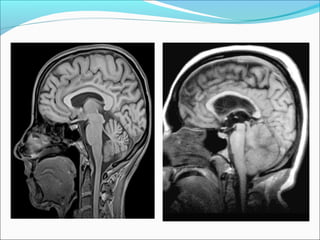

SUBFALCIAL HERNIATION

ļ‚—Subfalcial: displacement of the cingulate gyrus under

the free edge of the falx along with the pericallosal

arteries.

ļ‚—Can lead to anterior cerebral artery infarction

DESCENDING HERNIATION

Herniation:

Ascending Transtentorial

ļ‚—Cranial shift of

vermis and parts of

superomedial

cerebellar

hemisphere through

tentorium incisura

ļ‚— Compressed

superior cerebellar,

vermian cisterns and

forth ventricle

TONSILLAR HERNIATION

ļ‚—Inferior displacement of the cerebellar tonsils

through the foramen magnum

ļ‚—Can lead to posterior cerebellar artery infarction